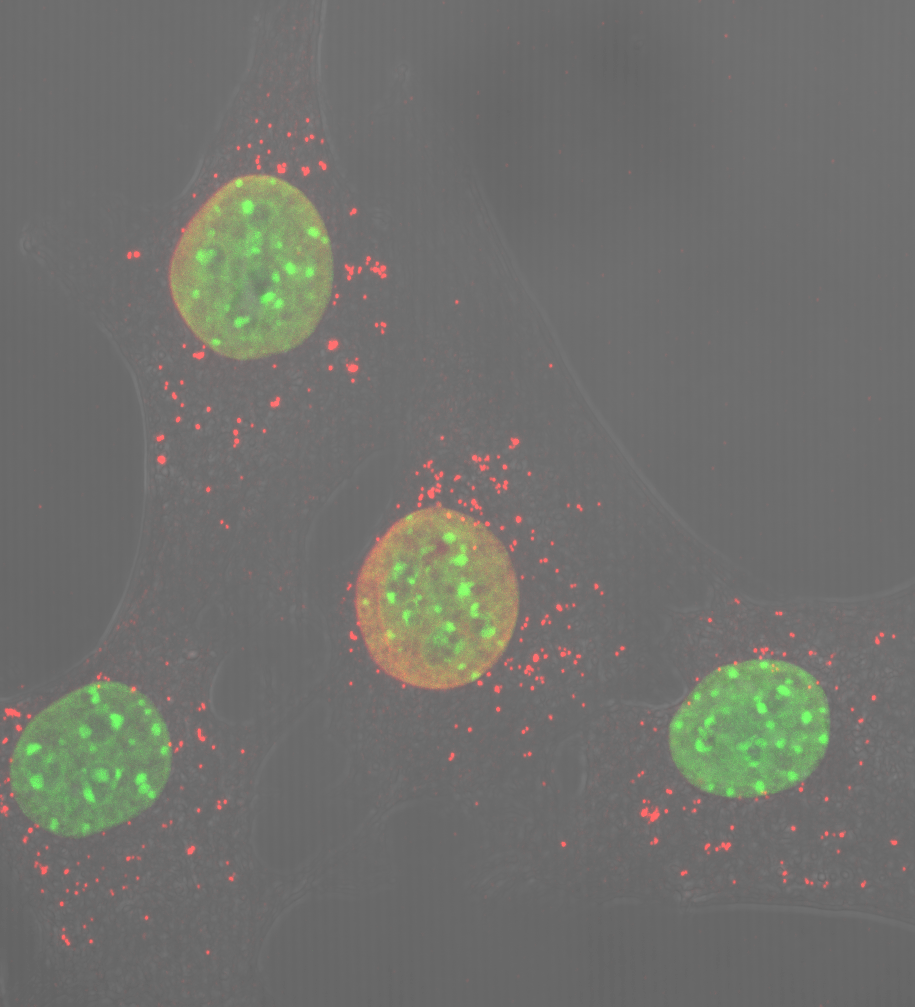

La falta de una única proteína mitocondrial genera inflamación severa